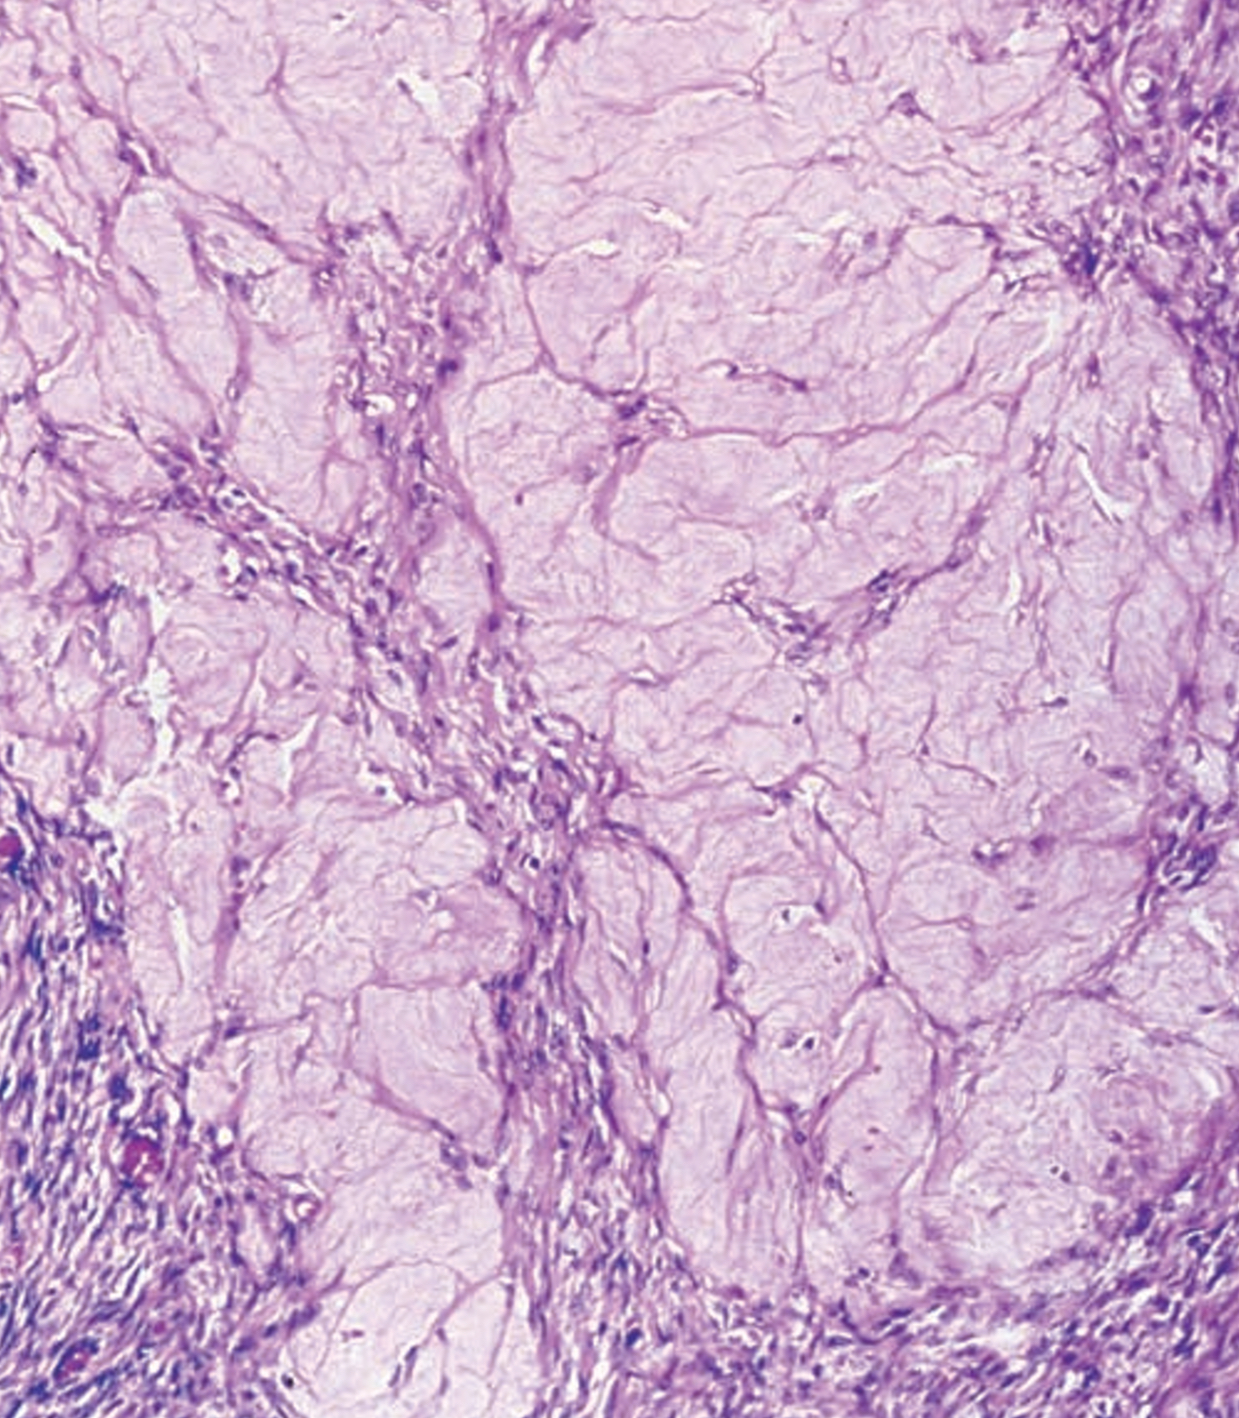

Neoplasia del canal auditivo

La neoplasia del canal auditivo, con el carcinoma de células escamosas como su manifestación más frecuente, representa un desafío clínico significativo debido a su potencial para mimetizar síntomas benignos como…